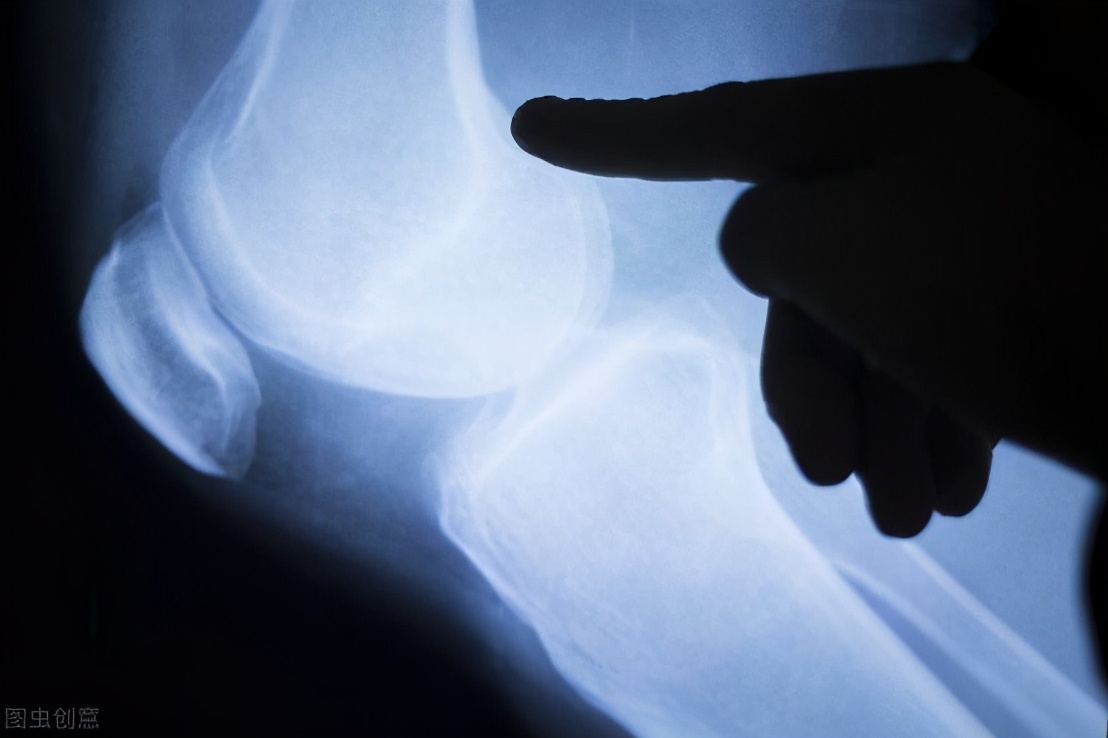

但是,随着大家运动热情的高涨,运动伤也逐渐引起重视,其中膝关节损伤尤为突出。

膝关节作为人体的重要关节,不仅承受着身体的重量,还维持着下肢的活动,相比其他关节更加脆弱。多数运动者往往不注重保护膝关节,从而出现韧带损伤、半月板损伤、滑囊炎和骨关节炎等多种运动损伤。

跑步、登山等运动,其实都是做重复的屈曲伸直动作,会使髌骨、胫骨与股骨承受巨大压力,长期如此,容易引起膝关节损伤。当你有如下表现时,就要警惕是不是自己的膝盖出现问题了: